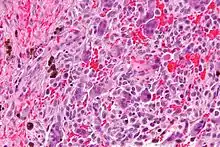

| Micrograph of a central giant cell granuloma showing the characteristic giant cells with surrounding cells that have nuclei that are dissimilar to those in the giant cells. H&E stain. | |

Histology of CGCG shows a lobulated mass composed of vascular connective tissue and multinucleated giant cells (osteoclasts). The giant cells may be diffusely located throughout the lesion or focally aggregate in the lesion, often clustered around hemorrhagic areas hemosiderin deposits. Lobules of the lesion can be separated by fibrous tissue or even thin layer of bone or osteoid that can be seen radiographically. Giant cells are thought to form in response to signals produced by fibroblasts and blood vessels or as a response to cytokines.[2][5]